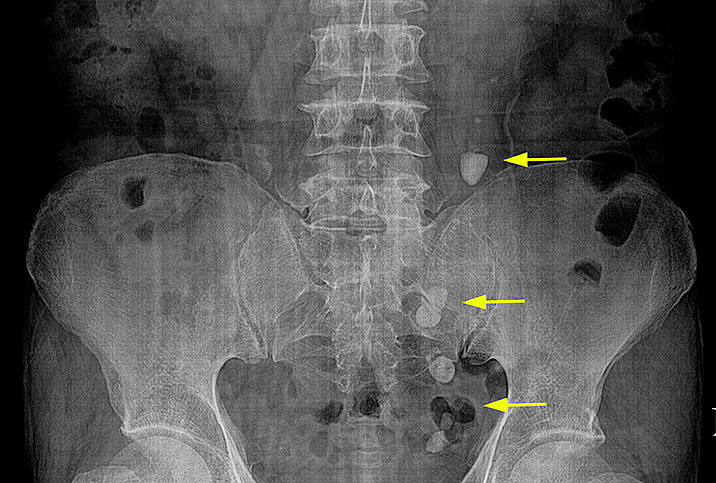

Изображения КТ конкрементов мочевого пузыря